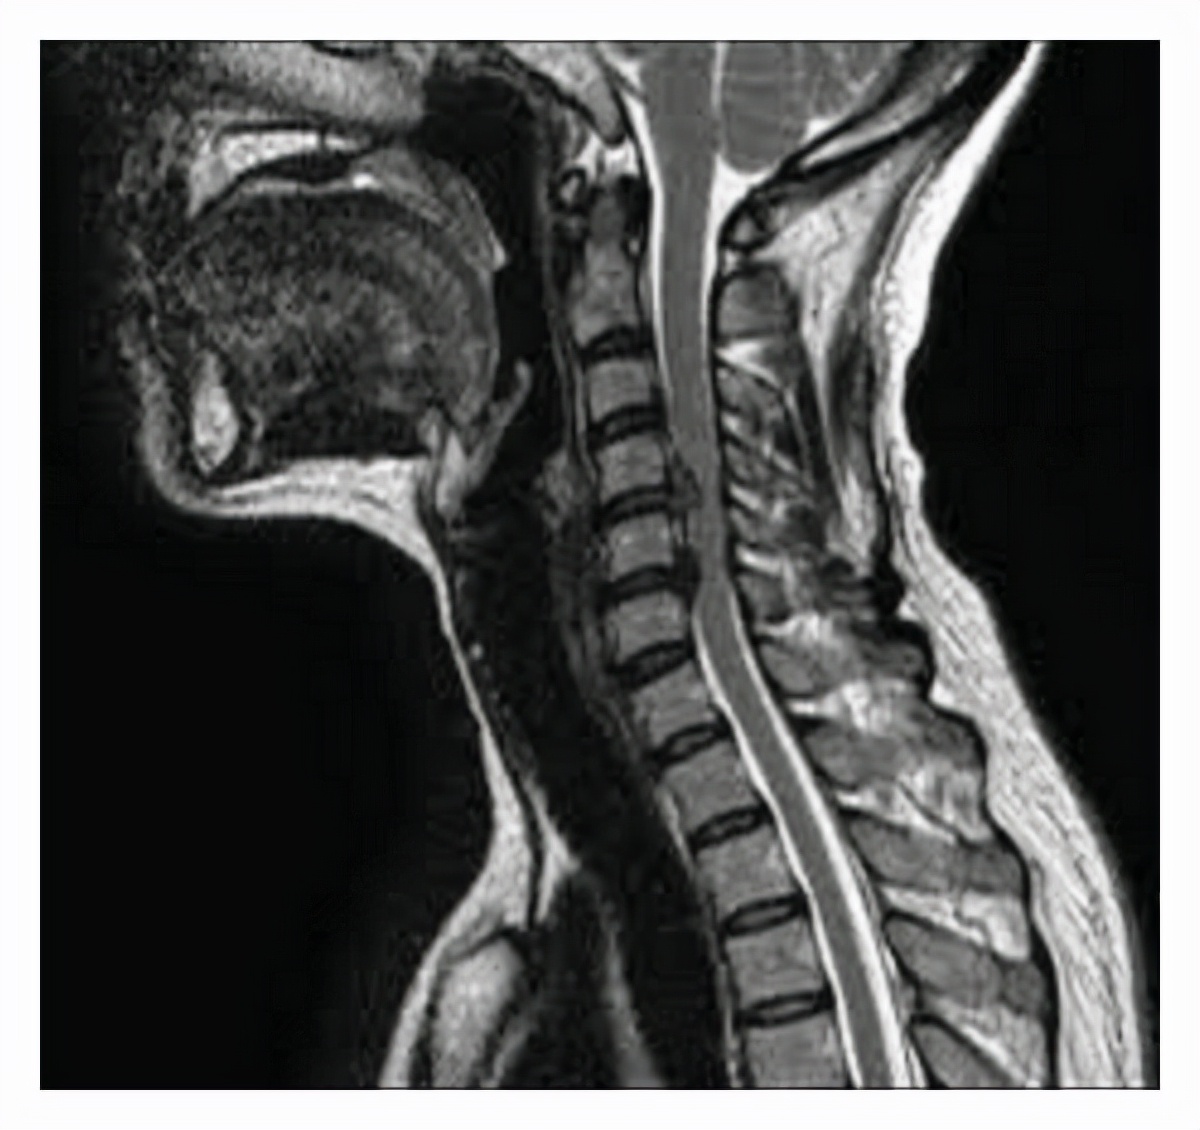

二、颈椎病 。颈椎病其实有很多种类型 , 如果长时间低头玩手机或者睡眠的时候 , 枕头真的太高 , 都可能导致颈椎不适的情况 。

但是要知道如果这种简单的颈椎问题慢慢发展为颈椎病 , 那就可能更加严重了 , 不单单是颈肩部的疼痛和不适 , 还有可能是手指的麻木 。

就像上面所说的 , 神经其实就是一根根电线 , 如果颈椎出了问题 , 在颈椎里面所通过的脊髓也会受到压迫 , 这就会导致电线有一部分出现了压迫 , 进而表现为麻木 。

当然这种麻木特点很典型 , 会出现在手部的内侧或者手指间 , 一般都会局限在某一个部位 。

而且除了麻木之外 , 还会有疼痛表现 , 这是颈椎病最常发生的情况 。

如果真的感觉是颈椎所导致的手指麻木有很多方式可以选择 , 但重点是及时就诊看看颈椎压迫到了什么程度 , 根据不同程度选择不同的治疗方式 , 这是很重要的 。